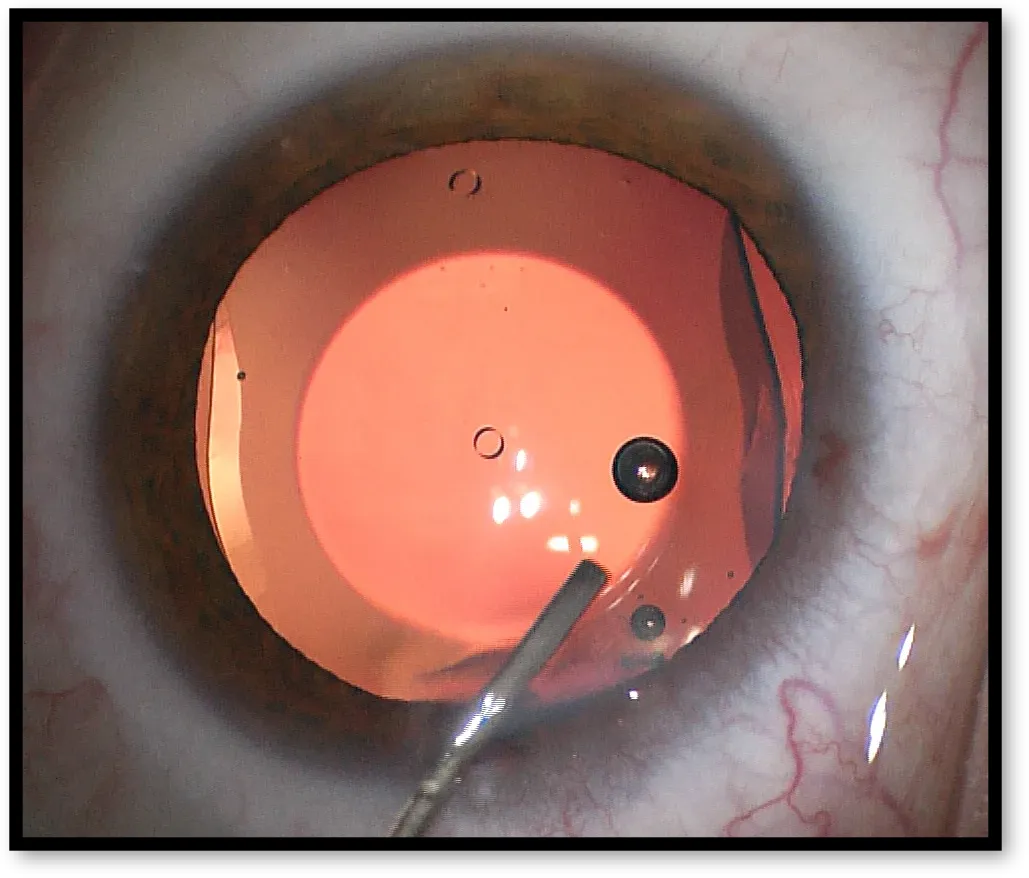

This program focuses on comprehensive training in diagnostic evaluation, surgical planning, and advanced refractive surgical techniques (LASIK, SMILE, Femto-LASIK, PRK, ICL).

Exposure to a high volume of refractive cases including LASIK, PRK, SMILE, ICL, and refractive cataract surgery.

Hands-on Surgical Experience

Opportunities to assist and perform under expert supervision, ensuring skill development and surgical confidence.

• Preoperative evaluation for ICL (Implantable Collamer Lens)

• Sizing, vault prediction, and patient counseling

• Hands-on ICL loading & insertion (wet lab/observation)

• ICL

• ICL – Indications, sizing, vault assessment

• ICL surgical technique & post-op care1